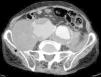

The patient was an 86-year-old man who was taking 2 medications for hypertension. He had a history of several months of low back pain that radiated to right thigh, for which symptomatic treatment provided partial relief. His rheumatologist had ordered thoracolumbar magnetic resonance imaging (MRI), but it was not performed because, prior to the scheduled date, the patient went to the emergency department with an increase in the intensity of the pain. Laboratory analyses showed a hemoglobin level of 8.4g/dL, lactate dehydrogenase of 318U/L, creatinine of 1.29mg/dL, C-reactive protein of 6.16mg/dL, erythrocyte sediment rate of 24mm/h and mild hypoproteinemia. There was no evidence of hemodynamic instability. He underwent abdominopelvic computed tomography (CT) with intravenous contrast, which revealed isolated bilateral iliac aneurysms>6cm (Fig. 1) with contained rupture of the aneurysm on the right (Fig. 2), which displaced the psoas muscle (Fig. 3) and perforated the ipsilateral iliac bone (Fig. 4). The patient underwent aortobifemoral bypass but, unfortunately, he died during the postoperative period.

Isolated iliac aneurysms, without an associated aortic aneurysm, are rare.1 They are relatively difficult to identify, as up to 40% of them may present with rupture.2 The incidence rate of extraspinal causes of sciatica is low.3 Likewise, chronic rupture of an aneurysm constitutes a peculiar entity. All these circumstances coming together result, in most cases, in an erroneous or late diagnosis.4 It is usually a dorsolateral rupture toward the anterior insertions of the psoas muscle, which contains the hematoma, avoiding massive extravasation, but not the infiltration of the roots of the lumbosacral plexus. This produces chronic low back pain that radiates to the lower limb,5 this being the most common presentation.6 The diagnosis can be based on abdominal CT,7 and lumbar MRI (parasagittal slices).7,8 The aneurysm may undergo secondary acute rupture at any time.4 This case serves to remind us, in our routine practice, that an aneurysm may be involved in the symptoms of sciatica.9